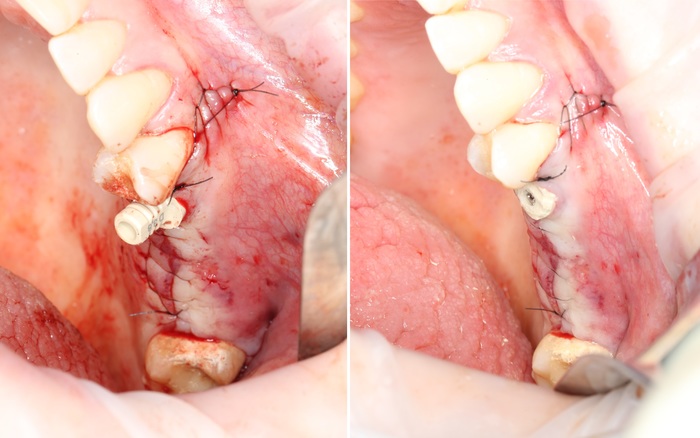

Дабы не перегружать вас обилием одинаковых картинок, я оставлю один рентгеновский снимок, но отмечу, что установка имплантатов на верхней и нижней челюсти проводилась с разницей в 10 дней.

На верхней челюсти было дополнительно удалено два боковых резца с одномоментной установкой имплантатов, так же они были установлены в области четверок и шестых зубов. Дополнительно было проведено наращивание костной ткани - двусторонний синус - лифтинг. О том, что это такое, можно почитать ТУТ и ТУТ.

После нехитрых манипуляций мы прощаемся с Русланом на 4 месяца.